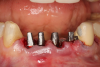

The next case follows the digital protocol for fully guided surgery and prosthetics. A CBCT radiograph, digital impression, and digital photography were the cornerstones to the success of this case. The 3D data set was electronically delivered to the dental laboratory. The data were merged and the process to develop the plan was initiated. The use of CBCT was essential in this case, particularly due to minimal space for placement of individual implants and single-unit crowns. The patient's chief concern was that she wanted to have single-unit crowns instead of fixed crown-and-bridge restorations because she was worried that she would someday find herself in an assisted-living facility; if that were to happen, she wondered, who would help floss under her bridge work? Her decision was to have single implants with individual crowns. CBCT technology is much more accurate in evaluating space maintenance and management.10 Periapicals in the past were rather close for calculating spacing; however, the CBCT identifies the buccal-lingual dimensions as well as the mesial-distal measurements. On review of the completed proposals for implant placement and provisionals, it was determined that there was sufficient spacing for implant placement to allow appropriate emergence profiles for the provisionals and then eventually the final single-unit cemented crowns. The proposal was accepted, and a 3D-printed surgical stent was fabricated, along with the PMMA provisionals (Figure 29 through Figure 35).

Fig 29. Preoperative Panorex.

Figure 29

Fig 30. Preoperative periapical radiograph.

Figure 30